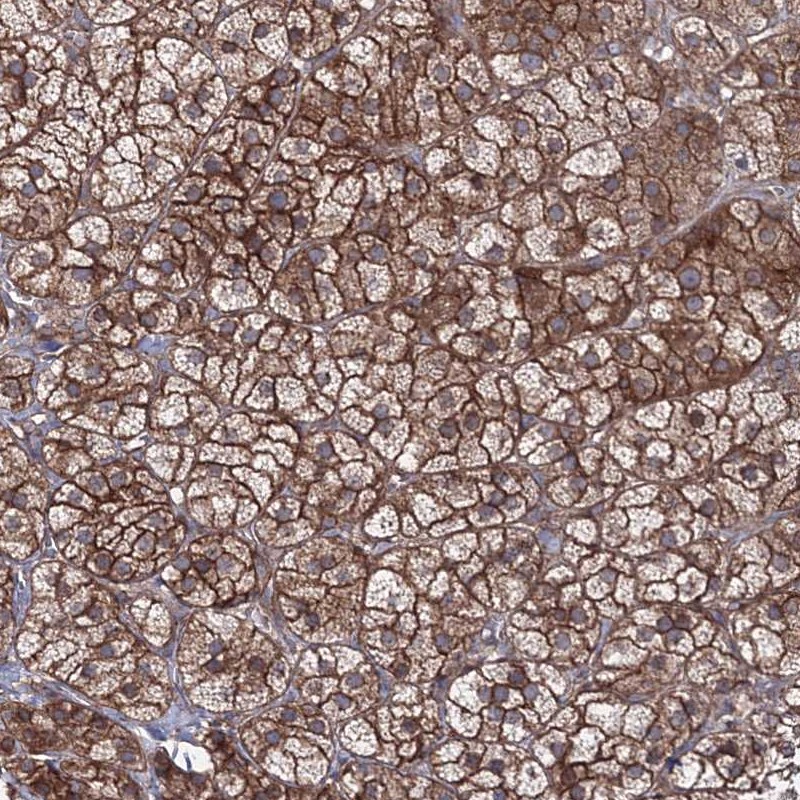

Immunohistochemical staining of human adrenal gland shows strong membranous and cytoplasmic positivity in cortical cells.